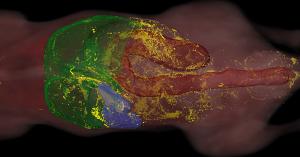

The Cleveland, Ohio-based company will use this two-year award to develop artificial intelligence (AI) techniques for detecting healthy and diseased tissues from preclinical microscopic images. The project is a collaboration with Dr. Susann Brady-Kalnay (co-Principal Investigator, Professor of Molecular Biology and Microbiology) and Dr. David Wald (Professor of Pathology) from Case Western Reserve University (Cleveland, OH). Currently, there is no existing imaging technology for a combined whole organismal level screening and targeted tissue collection. To mitigate this, BioInVision will develop an AI-driven software powered by CryoViz Imaging. “This award is a testament to BioInVision’s continued quest to develop technology that reduces the cost and time spent in animal research, improve efficiency of the discovery phase of developing new drugs, and accelerate the advancement to clinical trials,” stated Debashish Roy, President and CEO of BioInVision. Madhu Gargesha, Vice-President of Research and Project Principal Investigator, added “Instead of focusing on a single organ, users can image an entire organism, capturing multiple organs in 3D in high-resolution. AI-based software will enable automatic tissue-focused investigation and section collection to study the impact of disease at a cellular and molecular level”.

BioInVision is a privately held biotechnology company offering imaging instrumentation and methodologies critical to pre-clinical studies and AI-powered software for clinical applications such as cardiac CT perfusion. The patented CryoViz cryo-imaging technology is sold as an instrument and service for a variety of biomedical applications including stem cells, cancer, drug discovery, etc. Its global customers include life-scientists from academic and government institutions; biotechnology and pharmaceutical companies; hospitals and reference laboratories.

BioInVison's CryoViz Imaging Service empowers researchers with ultra-hi-res mouse-sized-field-of-view brightfield and molecular fluorescence imaging data